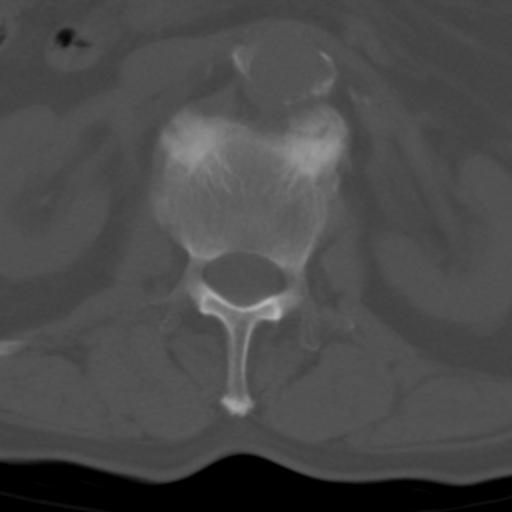

男性 82 主动脉夹层 请大家看看椎体是什么改变啊

腰椎退行性变,明显的骨赘形成,所指低密度灶为正常松质骨。